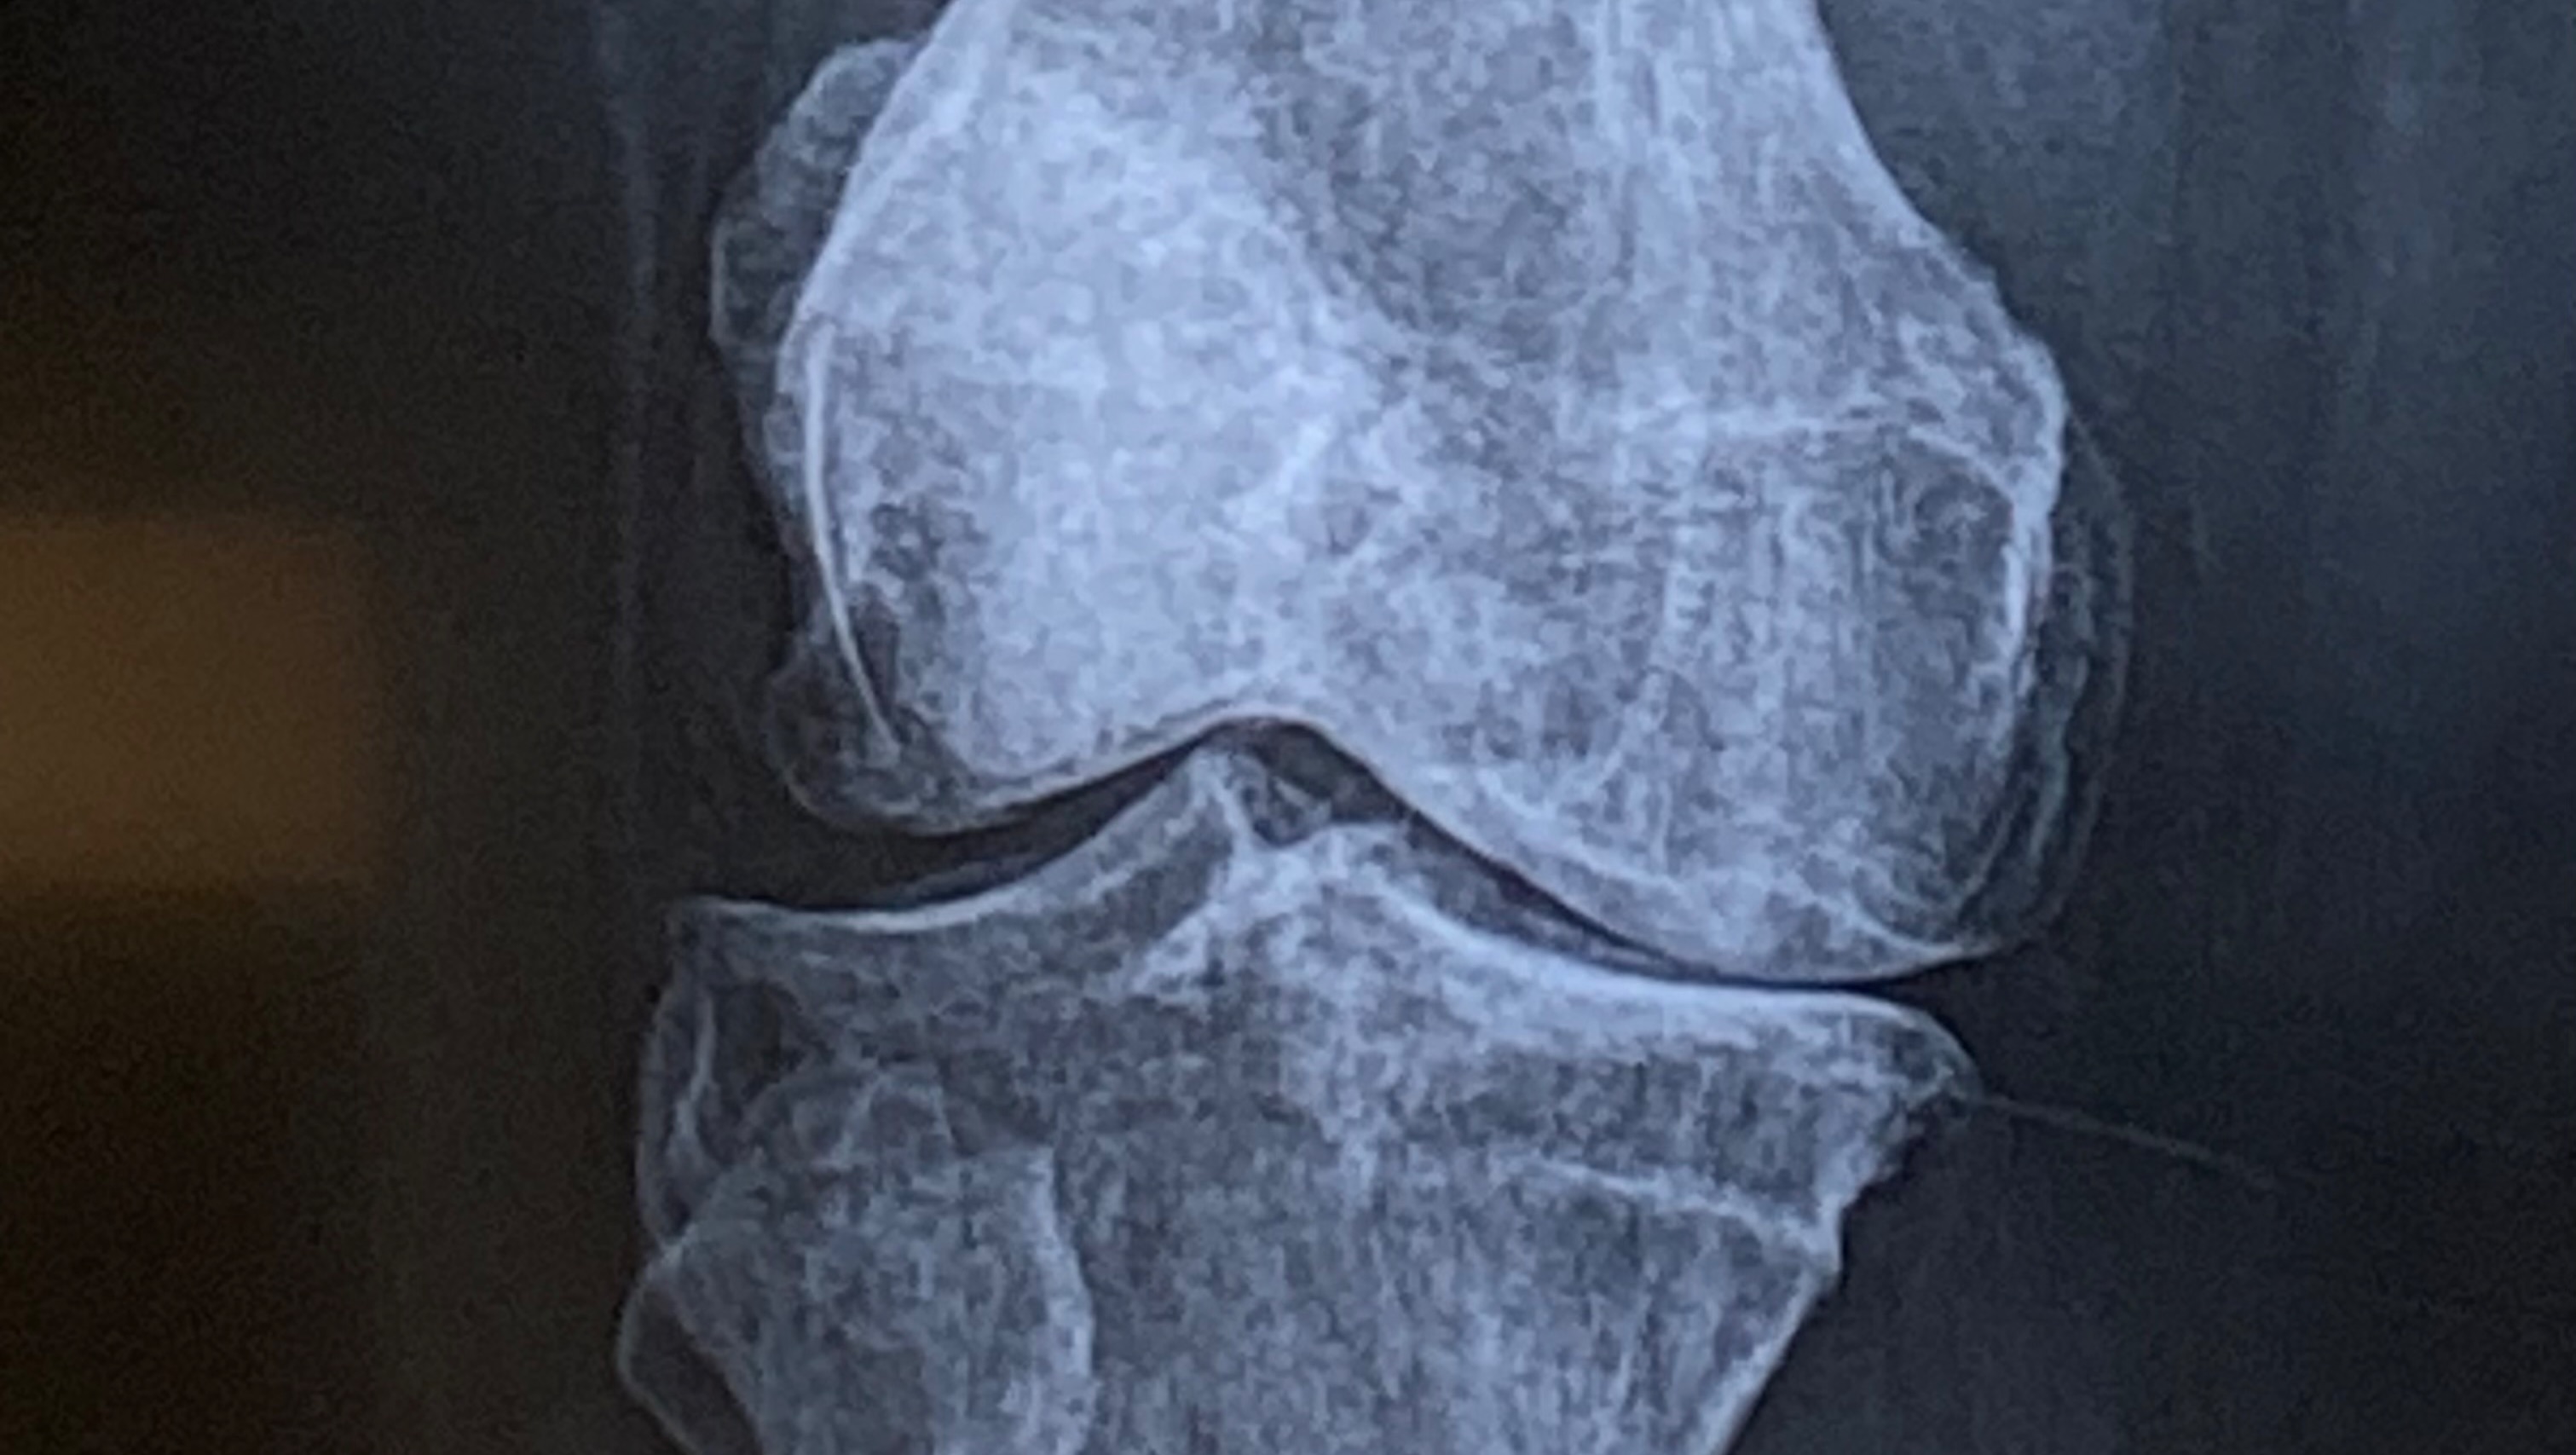

The pain in my knees is constant. I’m bone-on-bone in my left inner knee and right outer knee. It’s getting worse every single day. Walking is becoming nearly impossible, and without help, I’ll end up in a wheelchair permanently.

When I talked to my doctor about knee replacements, I was told it’s too risky for me. If I were to get an infection after surgery, I could lose my legs. The only option left for me is stem cell therapy – a much safer, non-surgical approach. But the problem is: insurance doesn’t cover it. Not mine, not anyone’s. It costs about $7,000-$8,000 per knee, and I need both done.